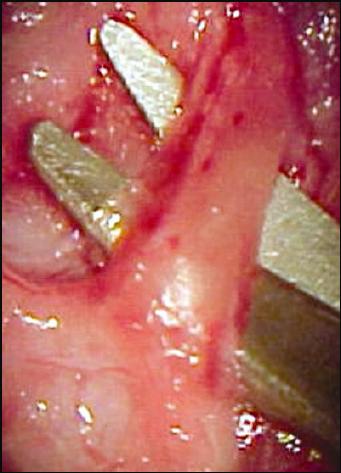

(Fig.1).

FIGURA 1: Animal na mesa operatória para cirurgia em nervo facial esquerdo.